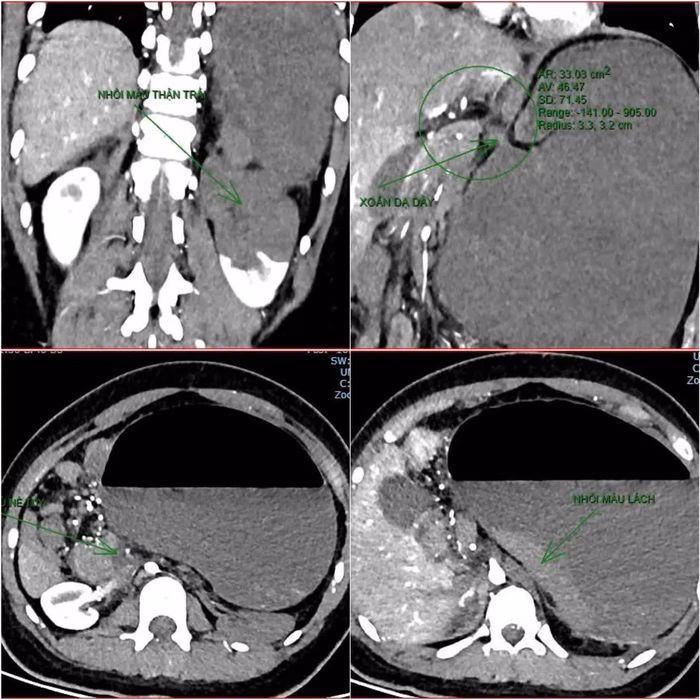

Kết quả chụp cắt lớp vi tính và hội chẩn liên khoa

Vào khoảng 21:40, kết quả CT cho thấy bệnh trạng phức tạp: xoắn dạ dày, nhồi máu thận trái, nhồi máu lách, viêm đầu tụy, viêm hỗng tràng kèm dịch ổ bụng và tràn dịch màng phổi. Đặc điểm này rất hiếm gặp ở bệnh nhân có hội chứng Down và tim bẩm sinh.

Trước tình huống nguy hiểm, các bác sĩ chuyên khoa Hồi sức tích cực, Chống độc, Cấp cứu, Ngoại tổng hợp, Chẩn đoán hình ảnh và Gây mê hồi sức đã họp hội chẩn liên khoa để đưa ra phác đồ mổ cấp cứu.